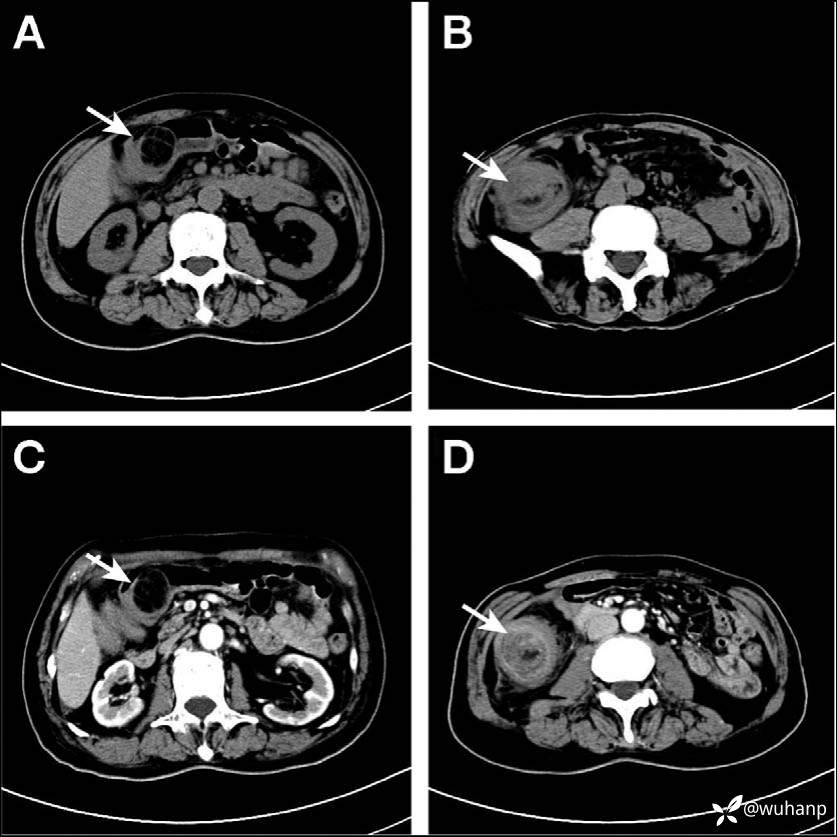

辅助检查:Hb 71g/L。AFP、CEA正常。腹部B超提示右上腹可探及7cm大小混合回声的肿块。腹部CT平扫提示结肠肝曲处广泛肠壁增厚,呈椭圆形(图A-D)。